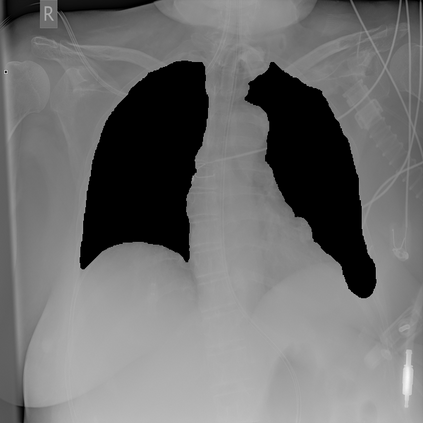

Deep learning technologies have already demonstrated a high potential to build diagnosis support systems from medical imaging data, such as Chest X-Ray images. However, the shortage of labeled data in the medical field represents one key obstacle to narrow down the performance gap with respect to applications in other image domains. In this work, we investigate the benefits of a curricular Self-Supervised Learning (SSL) pretraining scheme with respect to fully-supervised training regimes for pneumonia recognition on Chest X-Ray images of Covid-19 patients. We show that curricular SSL pretraining, which leverages unlabeled data, outperforms models trained from scratch, or pretrained on ImageNet, indicating the potential of performance gains by SSL pretraining on massive unlabeled datasets. Finally, we demonstrate that top-performing SSLpretrained models show a higher degree of attention in the lung regions, embodying models that may be more robust to possible external confounding factors in the training datasets, identified by previous works.